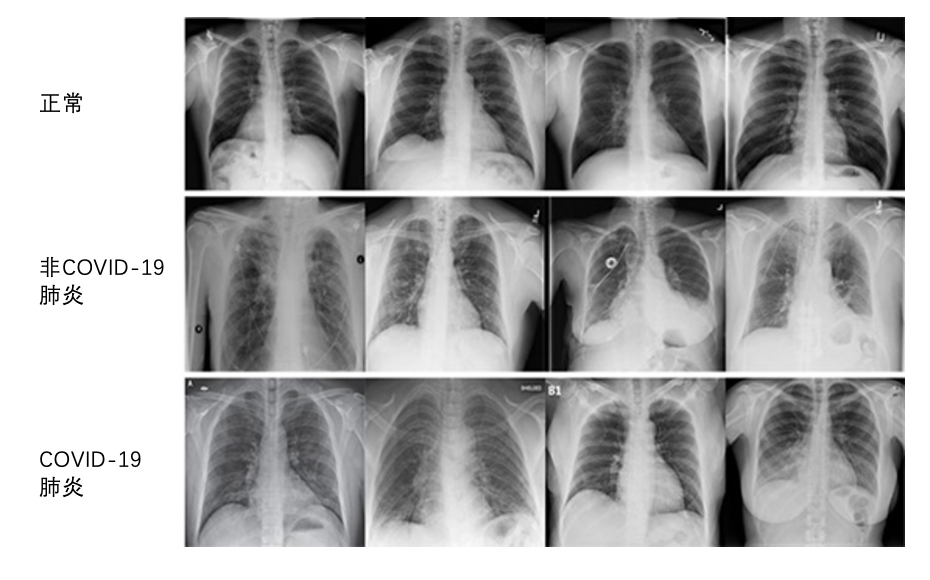

一項稱為F分數的測量對于深度學習系統的整體準確性進行了評估,該系統嘗試準確地預測數字圖像上的圖案和異常。康耐視的研究人員分析了COVID-Net數據集中的近14,000張X光片圖像。這些圖像被分為以下三種類型:正常、非COVID-19肺炎和COVID-19肺炎。